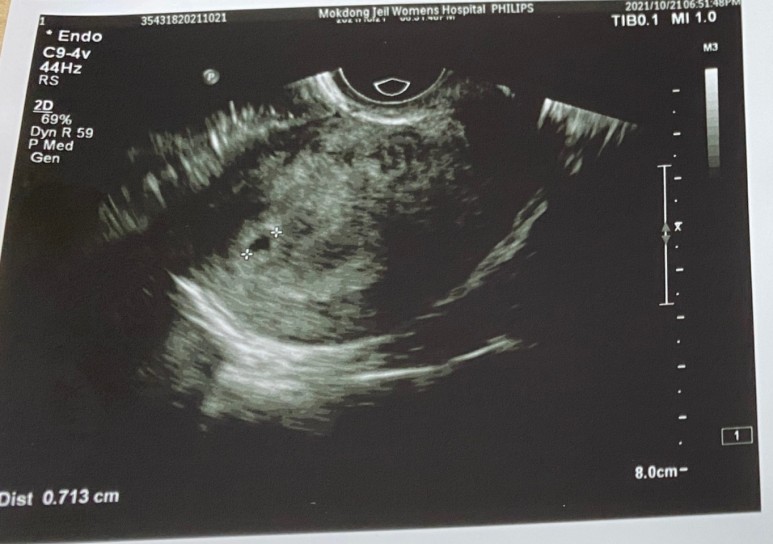

●11주 5일 소량 출혈로 방문

11주 5일 소량출혈로 방문! 화장실 갔다 왔다가 오줌 싸서 피인가 싶을 정도로 스며 나올 정도의 출혈 발견! 깜짝 놀라서 귀가하자마자 바로 병원 방문! 출혈은 온데간데없다는… 후후 다행인데 기가 죽는다^^;출혈이 있으면 STD검사를 필수라고 하기에 검사하도록 한다.